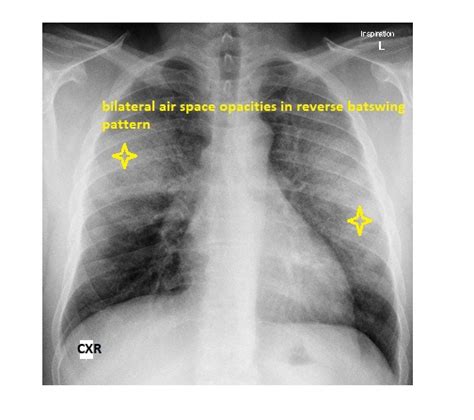

Alright, so let’s get down to brass tacks: what is this batwing appearance we keep talking about? When a radiologist – that’s the doctor who specializes in reading X-rays and scans – looks at a chest X-ray, they’re searching for specific patterns. The batwing appearance , also sometimes called a “butterfly pattern” or “perihilar infiltrates,” describes a very distinct look on the imaging. Imagine the central part of your chest, around your heart and the main blood vessels and airways (this area is called the hilum, or perihilar region). When there’s a significant amount of fluid, blood, or inflammatory material building up in the lungs, particularly around these central areas, it tends to spread outwards from the hilum, but spares the very edges or periphery of the lungs. This creates a silhouette that looks remarkably like a bat with its wings spread out, or a butterfly if you’re feeling more optimistic! These perihilar infiltrates are basically areas of increased density on the X-ray, meaning they look whiter or brighter than healthy lung tissue, which usually appears dark. The reason it spares the very edges (apices and costophrenic angles) is often due to gravity and the distribution of blood flow and lymphatics, which direct fluid away from these areas, at least initially. Understanding this visual cue is absolutely crucial because it immediately narrows down the list of potential problems, allowing doctors to hone in on the most likely lung conditions . It’s like a medical shortcut for diagnosis, providing a strong indication that there’s a significant process, often acute and severe, affecting both lungs symmetrically. So, when a doctor sees batwing appearance , they know they’re dealing with something that’s likely systemic and affecting the entire pulmonary system rather than a localized issue. This is why knowing about this sign is so important for healthcare professionals and, honestly, pretty fascinating for anyone interested in how our bodies work and how medical imaging helps uncover hidden truths. It’s a prime example of how a simple image can speak volumes about your health status, and why skilled interpretation is invaluable. The symmetry of the infiltrates, hugging the central lung fields while leaving the outer zones relatively clear, is the defining characteristic that makes this particular pattern stand out and earn its memorable, if slightly ominous, name. This distinct pattern is what helps clinicians differentiate it from other types of lung infiltrates, like those seen in typical pneumonia or localized tumors. Guys, it’s a major red flag that something significant is happening within your pulmonary system.